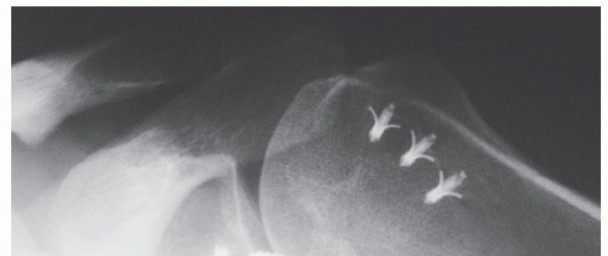

Hardware-related complications may occur owing to loosening; bending; or breakage of screws, anchors, or tacks (FIG 7).36 Synovitis in response to PLLA, absorbable implants has also been described.

Misplacement of labral tacks or suture anchors, both metallic and absorbable, may lead to early arthrosis

or arthritis.

FIG 7 • AP radiograph of a left shoulder showing loose hardware after a prior coracoid transfer procedure.*